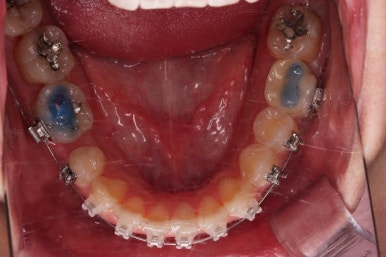

다행히 매복되었던 영구치는 잘 이동하였고요.

임플란트 자리도 적당한 크기로 점점 넓혀갑니다.

매복 영구치도 거의 다 배열되어 가고요.

임플란트 공간도 많이 확보되었습니다.